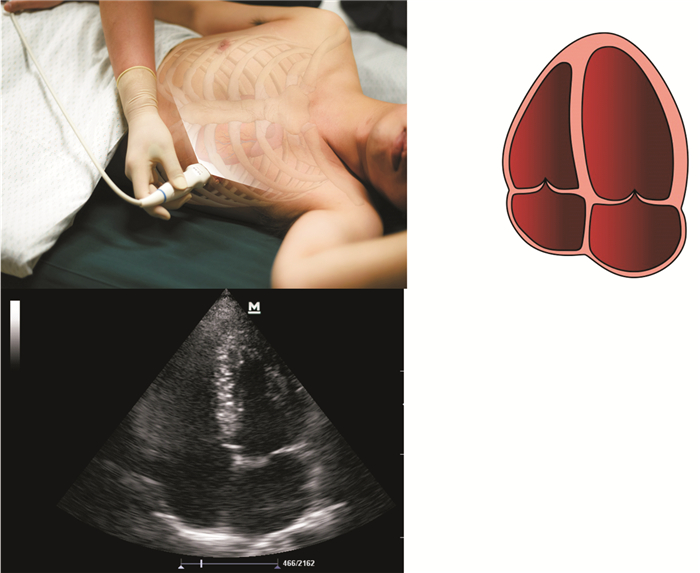

2.2.3 inferior vena cava (下腔静脉)

采用剑突下声窗下腔静脉纵切面,M超,测量下腔静脉内径、塌陷程度及变异率,估算中心静脉压,评估右心功能及容量状况,评估有无右心功能衰竭、肺栓塞、肺动脉高压等原因引起休克的间接证据 (图 9)。

图 9 心脏心尖两腔心切面

2.2.4 respiratory system (呼吸系统)

采用对称三点对双侧胸腔和肺进行超声扫查,对胸膜腔液性暗区、肺点、胸膜滑动征、A线、B线、沙滩征、平流层征、肺火箭征等肺部超声常见征象的存在与否进行筛查,协助明确,筛查有无张力性气胸、大量胸腔积液、积血引起的休克,寻找肺水肿等休克的表现协助明确休克类型及原因。因为张力性气胸是一种极为紧急的临床情况,且一经诊断能够通过引流迅速纠正梗阻性休克,改善循环状态,所以根据临床的症状及体征,当可疑张力性气胸时,应首先进行肺部超声扫查,明确该诊断 (图 4510)。

图 10 下腔静脉纵切面